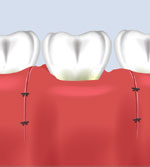

The "crown" is the part of a tooth visible above the gumline. Sometimes more of the tooth below the gums must be exposed to fill a cavity near the gumline or place a new crown on a broken tooth. "Crown lengthening" provides more tooth structure for this to be done. This helps to ensure that the general dental procedure is successful and prevents gum irritation.

Crown Lengthening ProcedureProcedure: The periodontist administers a local anesthetic and gently recontours excess gum and bone tissue to expose more of your natural tooth.